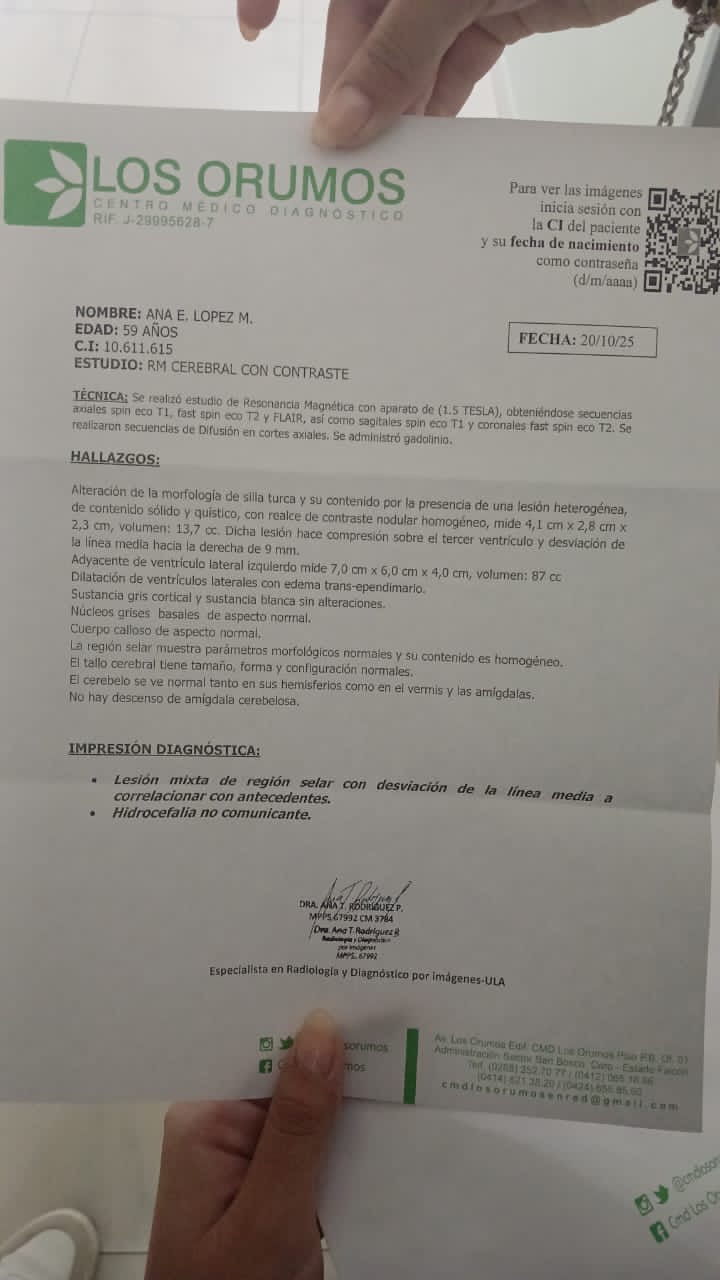

Hola, mi nombre es Yraida y estoy recaudando fondos para mi prima Ana, quien tiene varios quistes y dos tumores en el cerebro (adenoma hipofisario y craneofaringioma) y necesita una operación urgente.

Hello, my name is Yraida, and I am raising funds for my cousin Ana, who has several cysts and two brain tumors (a pituitary adenoma and a craniopharyngioma) and urgently needs surgery.